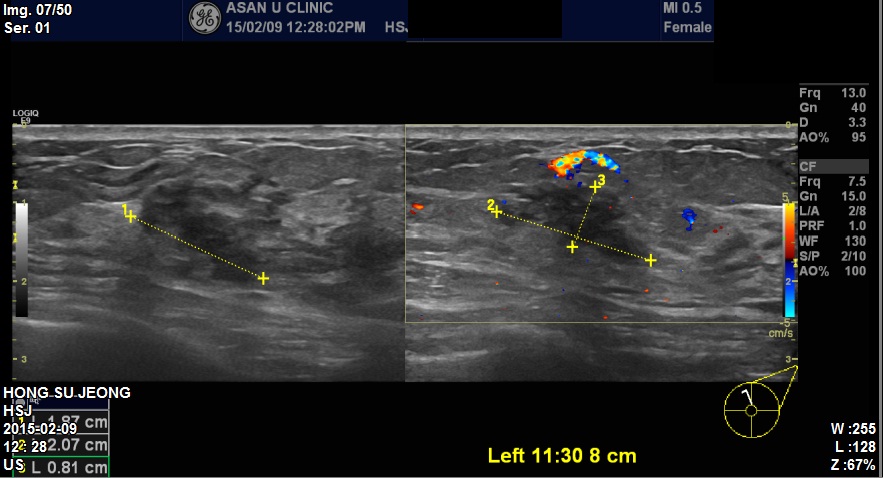

본원에 내원하신 50대 환자분이십니다.

좌측유방에 3개의 혹 조직검사시행하였고

상피내암 진단되었습니다. 감사합니다.